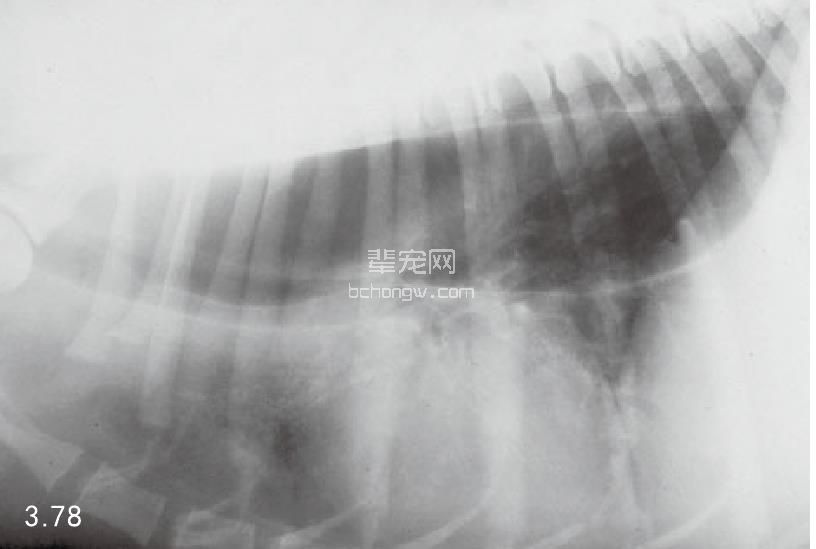

诊断 通过病史和胸腔常规X线片可以诊断 (图3.77~图3.80),但如果需要确定特殊的病 因,则需要进行额外的试验(表3.7)。如果不能 确诊可以做食管X线片和食管镜试验,但通常没有 这个必要(图3.81和图3.82)。德国牧羊犬、大丹 犬、爱尔兰赛特犬、小型雪纳瑞犬和硬毛 易患 先天性巨食管症。犬胃扩张-扭转综合征时,也 可能暂时性继发巨食管症。

图3.78和图3.79 在图3.77中所述幼犬的食道造影X线片可见食管的巨大扩张。